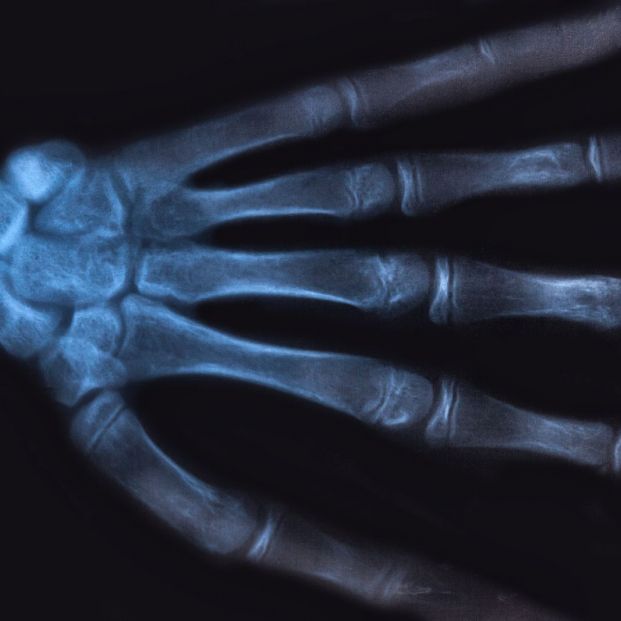

Causas y tratamiento de la osteoporosis

Según la Clínica Universidad de Navarra, la osteoporosis es “una enfermedad que se caracteriza por una disminución de la densidad de los huesos a causa de la pérdida del tejido óseo normal. Esto conlleva una disminución de la resistencia del hueso frente a los traumatismos o la carga, con la consiguiente aparición de fracturas”.

Estas lesiones se pueden producir en todo el cuerpo, pero las zonas más comunes son la cadera, el fémur, el húmero, la muñeca y las vértebras. No son rupturas espontáneas sino que suelen ser coincidencia por impactos o caídas leves, en las que un hueso en “plenas funciones” no se habría roto. Del mismo modo, el dolor de la osteoporosis viene por esta fractura, no antes de ella. Un dolor que no siempre está presente ya que hay fracturas que pasan desapercibidas, sin dar síntomas, y es en otra exploración cuando salen a la luz.